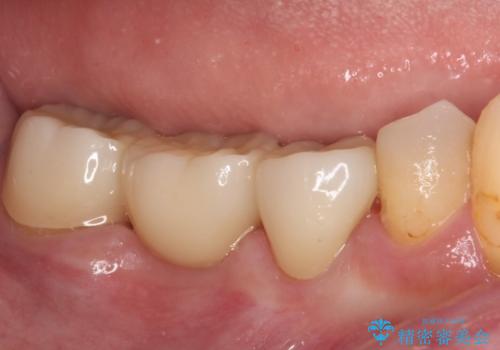

ただし、インプラント以外にブリッジでの補綴治療も可能であったので、抜歯後に治癒を待って、フルジルコニアブリッジにて補綴することとしました。

インプラント治療が回避でき、前後の銀歯も合わせてセラミックにできたので、患者様には大変満足していただきました。